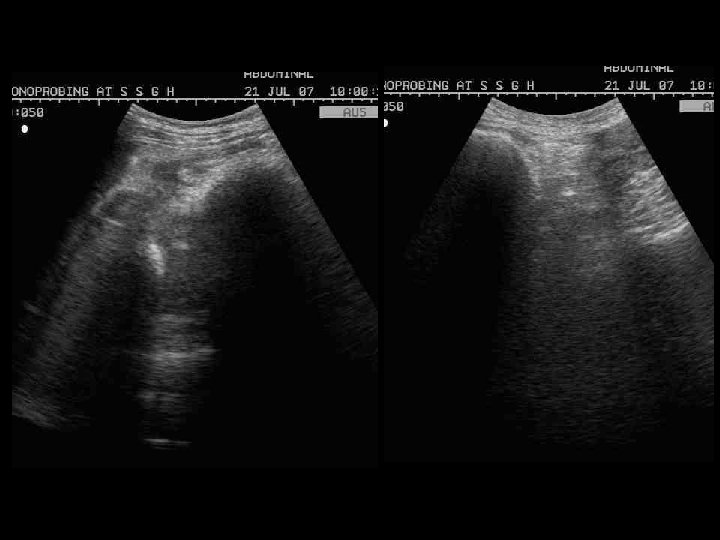

Abdominal US showing a dense, echogenic rim & broad bands with sharp, clear posterior acoustic shadowing in the epigastric region & within bowel loops.

• US, demonstrates a superficially located broad band of high amplitude echoes along the anterior wall of the mass with sharp, clean posterior acoustic shadowing. • This characteristic appearance persists irrespective of the angulation of the transducer, alteration of position of the patient and the administration of clear water. • This can be attributed to multiple tiny interfaces between the smooth, compressed, compact mass and the entrapped air and food debris.

• This specific US appearance excludes the clinical possibility of a pancreatic pseudocyst, splenic or renal mass, non-calcified gastric tumor, gastric duplication cyst and gastric outlet obstruction. • However a heavily calcified mass such as teratoma, neuroblastoma or impacted mass of feces may produce a similar US image. • The sharp, clean margins of the acoustic shadow rule out the possibility of gas and which produce "dirty" shadowing.